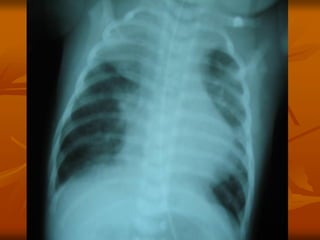

3. X QUANG PHỔI

 Không đặc hiệu:

Có thể BT: 13 % trẻ NV có XQ BT

 DH thường gặp:

 Ứ khí phế nang

 Thâm nhiễm mô kẽ, quanh PQ, PN

 Xẹp phổi: thùy trên phải

 Đông đặc phổi: 24%

 DH hiếm gặp: Tràn khí MP-TK trung thất (1%)

Tràn dịch MP

3. X QUANGPHỔI  Không đặc hiệu: Có thể BT: 13 % trẻ NV có XQ BT  DH thường gặp:  Ứ khí phế nang  Thâm nhiễm mô kẽ, quanh PQ, PN  Xẹp phổi: thùy trên phải  Đông đặc phổi: 24%  DH hiếm gặp: Tràn khí MP-TK trung thất (1%) Tràn dịch MP